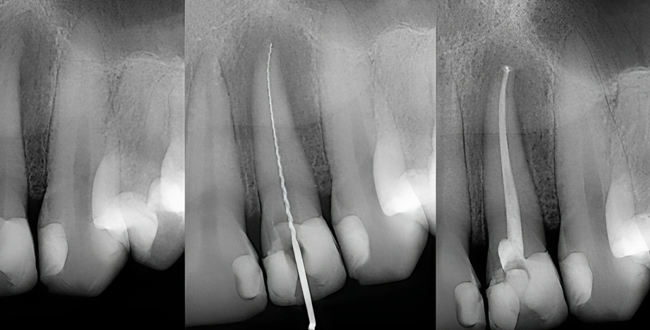

- Diagnosis: The endodontist assesses the patient's condition, typically using X-rays and clinical evaluation to determine the extent of pulp damage or infection.

- Access Opening: An opening is created on the back side of the tooth’s crown to access the root canal system. This allows the endodontist to clean and disinfect the inside of the canal space.

- Disinfection: Once the canal has been disinfected, the endodontist places either an antibiotic into the cleaned canal, or another medicament called calcium hydroxide into the canal, depending on the history of the tooth (trauma), and a temporary filling is placed.

- Tissue Stimulation: After the allotted time necessary, the patient returns, and the temporary filling and medicines are removed. A blood clot is induced from the stem cells outside.

- Sealing: The access opening is sealed, and the tooth is restored with a filling or crown, depending on the extent of the procedure.